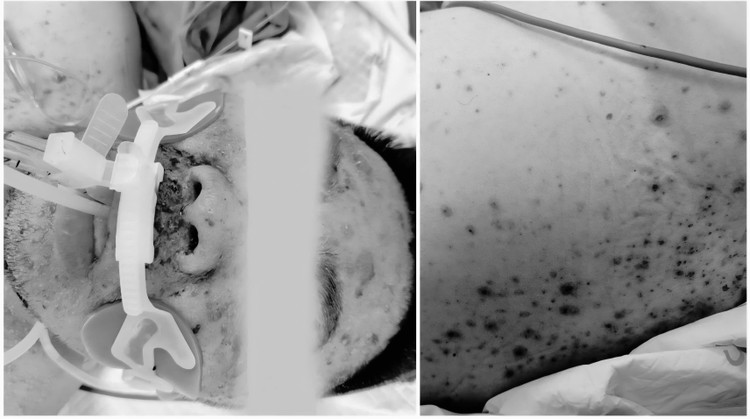

Ngày 31/7, Bệnh viện Bạch Mai cảnh báo đỏ về nỗi đau mang tên thủy đậu. Theo đó, bệnh nhân nam, 30 tuổi, vào viện trong tình trạng nguy kịch, tiên lượng xấu do biến chứng thủy đậu nặng nề.

Bệnh nhân có tiền sử hội chứng thận hư 7 năm, đang dùng thuốc ức chế miễn dịch, nhưng không có biện pháp phòng ngừa khi tiếp xúc trực tiếp với người mắc bệnh. Biện pháp đơn giản nhất là tiêm phòng vắc xin bệnh nhân cũng chưa từng thực hiện.

Dù đã được điều trị tích cực bằng thuốc kháng virus và các biện pháp lọc máu hiện đại, nhưng tình trạng suy gan tối cấp, suy đa tạng, rối loạn đông máu nghiêm trọng của bệnh nhân không được cải thiện.

Bệnh nhân bị thủy đậu nguy kịch - Ảnh BVCC